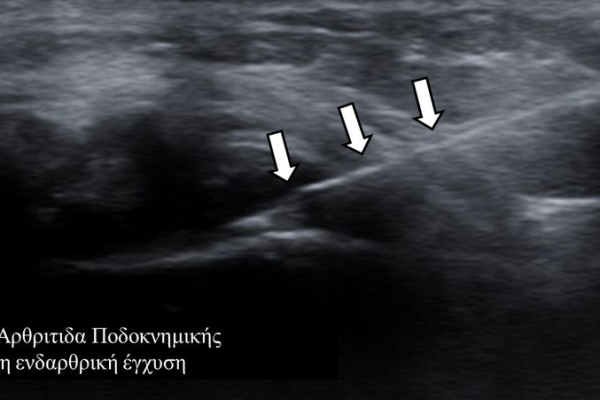

Οι διαγνωστικές-θεραπευτικές εγχύσεις είναι δυνατόν να γίνουν σε μια πλειάδα μυοσκελετικών-ρευματολογικών παθήσεων όπως:

- ενδοαρθρικά(πχ οστεοαρθρίτιδα)